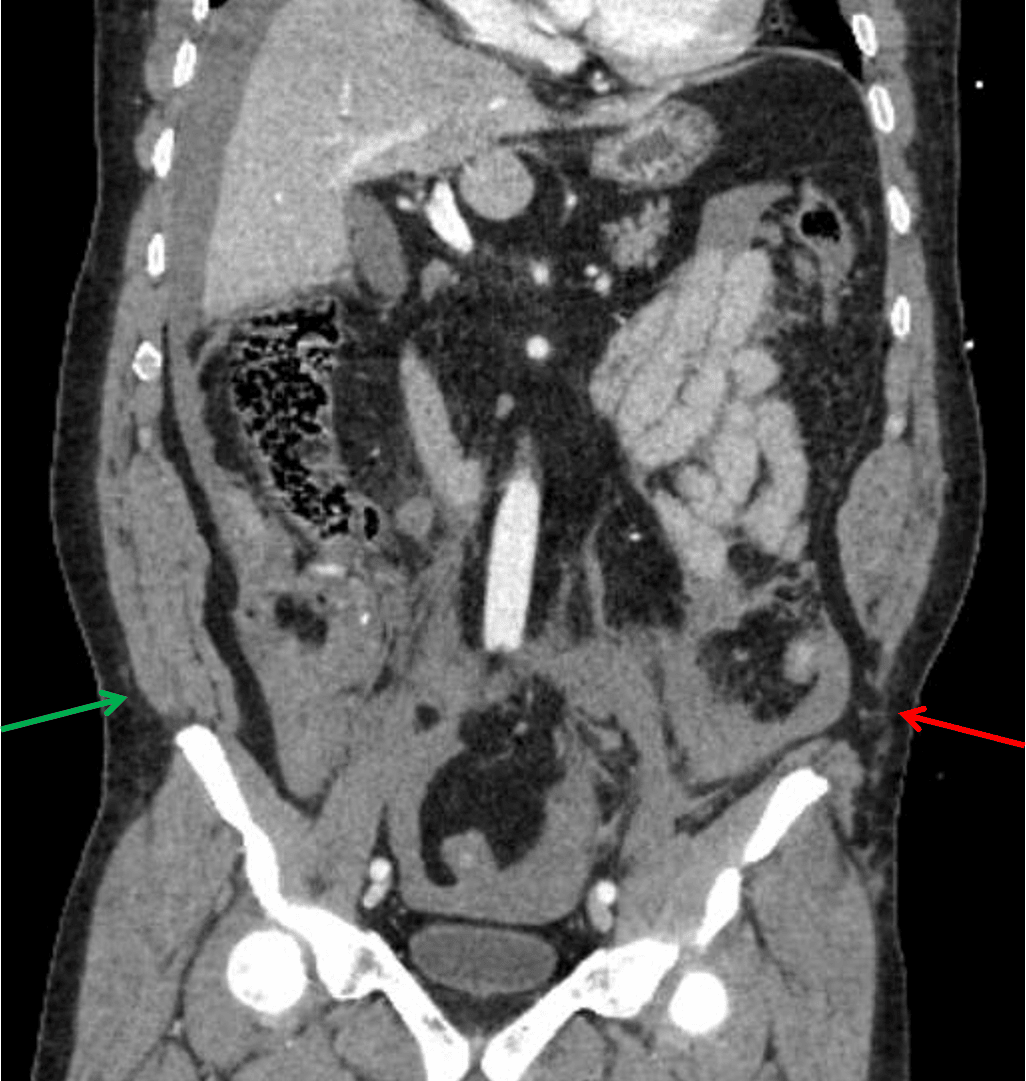

- Traumatic rupture of all fascial layers of the left lateral abdominal wall near their attachment on the left iliac crest resulting in a lumbar hernia, which only contains fat

Traumatic lumbar hernia

Acute left lumbar hernia with herniation of abdominal fat through the defect.

- This case also shows a good example of a traumatic lumbar hernia, as shown in an annotated image below. While rare, these indicate severe shearing forces and can unfortunately easily be missed by clinicians and radiologists in polytrauma cases

Traumatic herniation of the abdominal wall musculature from the left iliac crest (red arrow) compared to the normal appearance on the right (green arrow).